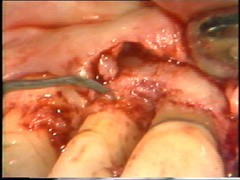

Remoción del tejido de granulación, dentina, cemento  infectado y cálculos

Se realiza una segunda  insición horizontal en el fondo de la bolsa  para facilitar el levantamiento del tejido de granulación

El levantamiento del tejido de  granulación se realiza en un tiempo y el procedimiento en sí es exigente. Puede hacerse antes o después del levantamiento del colgajo. El sangrado  se controla bien y el tiempo de exposición del hueso al medio bucal es reducido, cuando el tejido de granulación es eliminado antes del levantamiento del colgajo.

Observese como se ha eliminado el tejido de granulación en el segundo premolar.

Eliminación del tejido de granulación